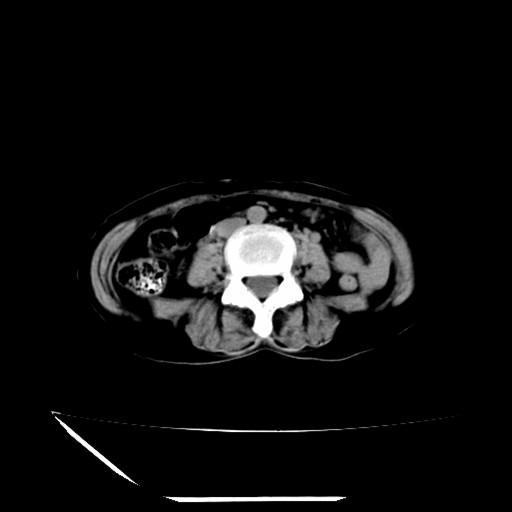

标题: CT16840:女-63岁,下腹部疼痛,

补充资料:血象是13.5,临床拟诊阑尾炎

道格拉斯窝内少量积液。

支持 阑尾炎,盆腔少量积液。